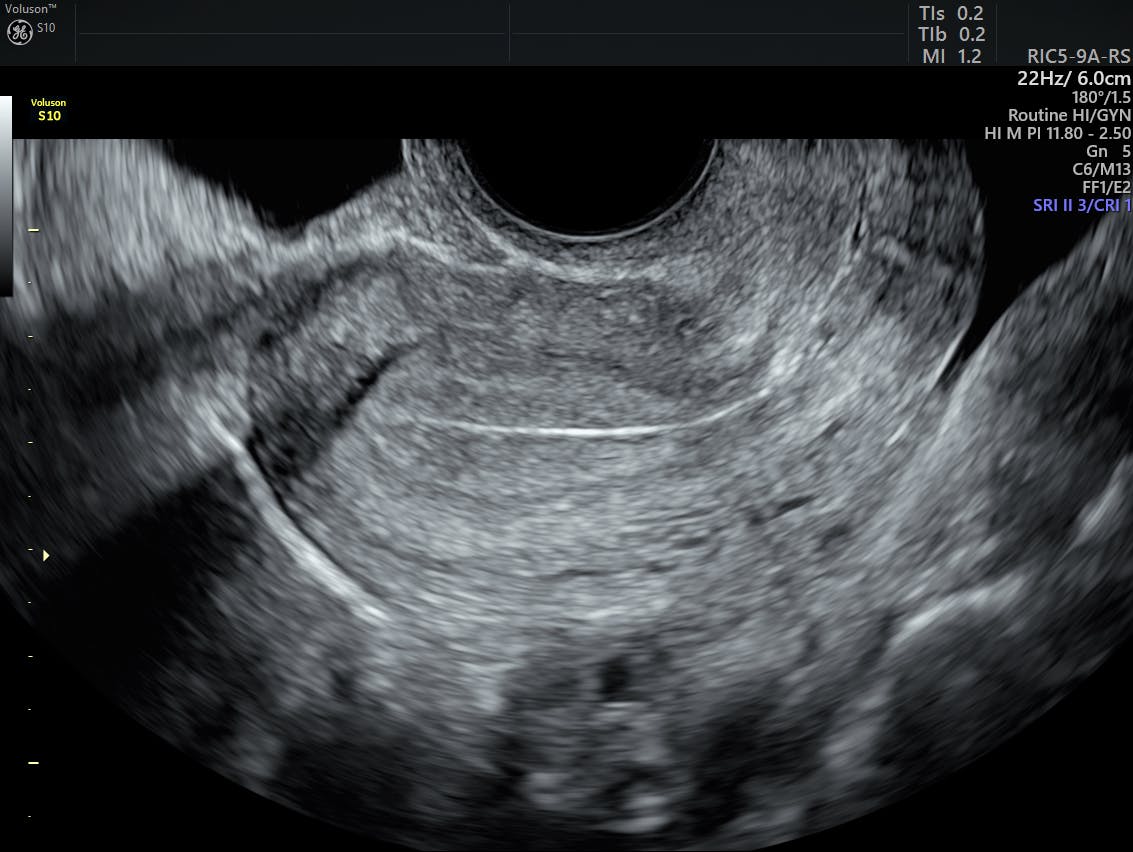

Time ultrasound to end of menses when endometrium is thinnest (if still menstruating) endometrial biopsy for stripe >5 mm; Female pelvic floor dysfunction encompasses a number of prevalent clinical conditions including urinary and faecal incontinence, obstructed defaecation, sexual dysfunction and female pelvic organ prolapse (fpop). Sep 27, 2018 · too many times i've seen women ignore abnormal bleeding or pelvic pain because they think it's "normal." in reality, these symptoms can be signs of abnormal cell growth in the uterus, also known as the "womb," a major female reproductive organ. Jul 28, 2021 · pelvic inflammatory disease is an acute ascending polymicrobial infection of the female gynaecological tract that is frequently associated with or. A pelvic ultrasound is a noninvasive diagnostic exam that produces images that are used to assess organs and structures within the female pelvis.

Time ultrasound to end of menses when endometrium is thinnest (if still menstruating) endometrial biopsy for stripe >5 mm; A pelvic ultrasound is a noninvasive diagnostic exam that produces images that are used to assess organs and structures within the female pelvis. The uterus contains various types of cells to help women carry a baby. Jul 28, 2021 · pelvic inflammatory disease is an acute ascending polymicrobial infection of the female gynaecological tract that is frequently associated with or. We are pleased to announce a new free case based urology learning program from the cleveland clinic glickman urological and kidney institute, rainbow babies and children's hospital, and university hospitals case medical center. Abnormal uterine bleeding (aub) in women of childbearing age is defined as any change in menstrual period frequency or duration, a change in amount of flow or any bleeding between cycles. If a male sonographer is doing the scan, there will need to be a female chaperone present for the transvaginal or translabial portion of the exam. Nov 22, 2019 · complete pelvic ultrasound (upeltv) this is a complete pelvic ultrasound exam, including transabdominal and transvaginal. Cancer is very unlikely if stripe <4 mm (negative predictive value 99.3%) incomplete imaging in 10% of cases Female pelvic floor dysfunction encompasses a number of prevalent clinical conditions including urinary and faecal incontinence, obstructed defaecation, sexual dysfunction and female pelvic organ prolapse (fpop). Change of address (except japan): In postmenopausal women, aub includes vaginal Sep 27, 2018 · too many times i've seen women ignore abnormal bleeding or pelvic pain because they think it's "normal." in reality, these symptoms can be signs of abnormal cell growth in the uterus, also known as the "womb," a major female reproductive organ.

A pelvic ultrasound allows quick visualization of the female pelvic organs and structures including the uterus, cervix, vagina, fallopian tubes and ovaries. Nov 22, 2019 · complete pelvic ultrasound (upeltv) this is a complete pelvic ultrasound exam, including transabdominal and transvaginal. Symptoms and physical findings vary widely and may include lower abdominal tenderness, adnexal tenderness, and cervical motion tenderness. Female pelvic floor dysfunction encompasses a number of prevalent clinical conditions including urinary and faecal incontinence, obstructed defaecation, sexual dysfunction and female pelvic organ prolapse (fpop). The latter is the most common condition and most likely to require surgical treatment.